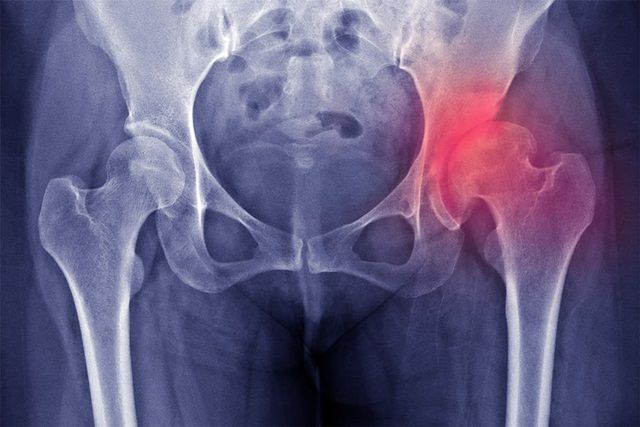

- Định nghĩa: trật khớp háng bẩm sinh là tình trạng chỏm xương đùi của một hoặc cả hai bên khớp háng bị trật ra khỏi vị trí bình thường (ổ cối) của khớp háng.

Trật khớp háng bẩm sinh là thuật ngữ y khoa chỉ tình trạng chỏm xương đùi nằm lệch một phần hoặc hoàn toàn bên ngoài ổ khớp háng. Khớp háng có thể bị trật một bên hoặc cả 2 bên. Tình trạng này còn được gọi là loạn sản khớp háng.